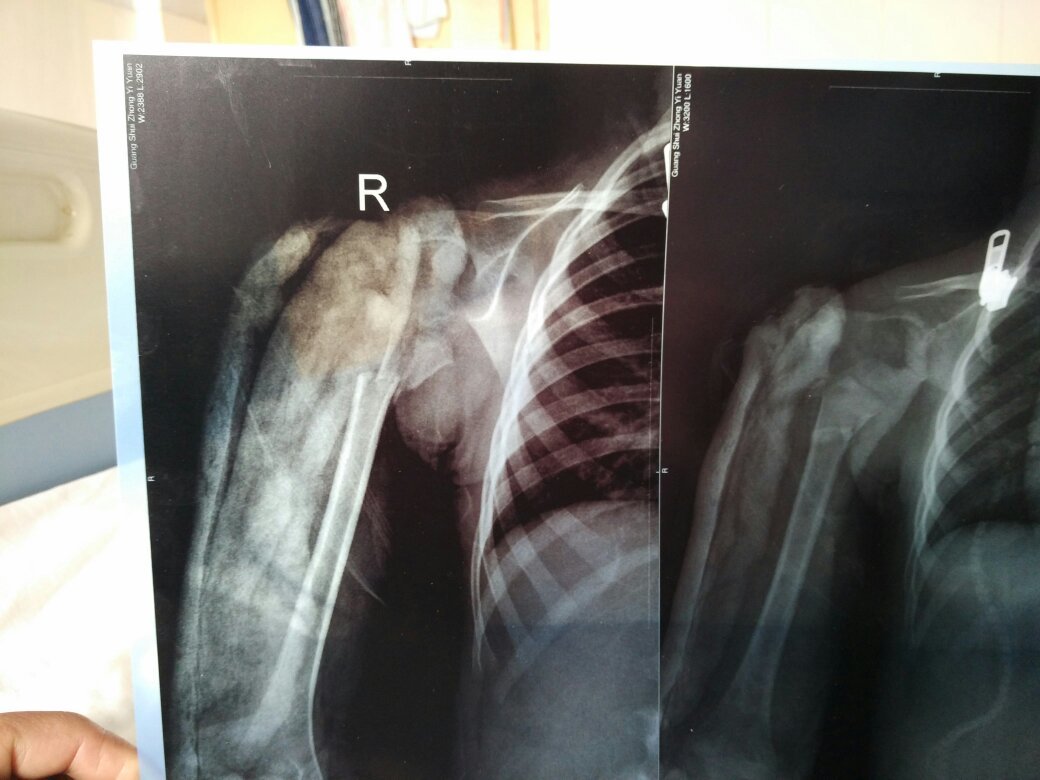

4岁小孩子肱骨骨折,打石膏固定了一个月,从拍出来的照片上来看,有一些错位,而且还比较多,医生却说问题不大。我怕影响以后的,毕竟是男孩子还是右胳膊,怕长大以后干不了重活。

中医和西医对于骨折的满意度是不一样的,中医讲究对位对线都要好,严丝合缝才是院玻成功的,西医不同,只要府套对位达到4/5以上就算手术成功。理由是,骨折位会慢慢长好,没对准的位置会被破骨细胞吸收、修复,特别是小孩子的骨折,将来会辉险亲完全愈合,只不过会有点弯,没有正常骨骼那么直,但是问题不大。